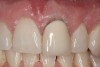

Achieving outstanding esthetics with implant dentistry is a reality (Figure 11 and Figure 12). Restorative efforts require disciplined steps to attain predictable results. To paraphrase my mentor, Cary Shapoff, DDS, renowned for his knowledge of periodontal disease treatment, bone grafting procedures, and dental implant surgery, implant esthetics is a series of well-planned, well-executed small steps that add up to a successfully restored fixture.